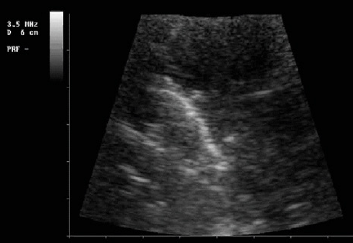

La diagnostica dei versamenti pleurici è agevole ed accurata. Il versamento è ben visibile (Figura 1), anche se in piccola quantità, e caratterizzabile (transonico, corpuscolare, fibrinoso, areolare). Anche i versamenti saccati sono diagnosticabili. L’ecografia è molto più accurata della radiografia standard per i versamenti. Infine il drenaggio di un versamento risulta più sicuro con l’impiego dell’ecografia 4 5.

Figura 1.Versamenti pleurici. In alto: versamento pleurico transonico (scompenso cardiaco). In basso: versamento pleurico complesso settato (empiema).